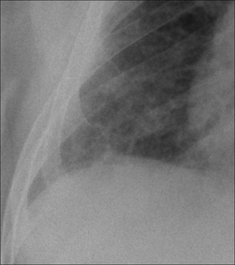

Figure 28.4 Acute dyspnoea. Left dome of the diaphragm appears to be high. Apply Golden Rule 3—you only look for what you know. Note the inferior displacement of the stomach air bubble. CXR conclusion—large subpulmonary effusion, not an elevated dome of the diaphragm (See p. 82).